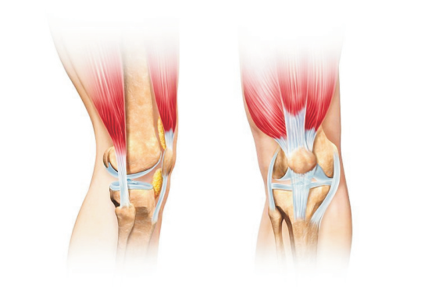

7、干细胞骨关节修复

国内治疗情况

中国骨关节炎患者的常规治疗包括口服消炎药止痛和氨基葡萄糖类药物、关节腔内注射玻璃酸钠、物理治疗和外科手术等,但效果并不理想。

美国骨科医师学会(AAOS)唯一推荐的骨关节炎治疗药物为非甾体类抗炎止痛药,然而该类药物却无法延缓关节软骨磨损和骨关节炎的进展。

干细胞修复原理

干细胞通过关书腔内注射,达到关节腔能够进行长期的自我复制,生长,分化,增殖,可以适应不规则的骨缺损及软骨缺损,促进半月板和骨体积增加,还可以加速不全撕裂的肌腱韧带的愈合,有效改善关节功能。

(多向分化,自我更新)

干细胞在不同分化发育阶段,细胞数量发生动态变化,分泌活性因子,促进细胞基质成分生成,并促进血管生成,改善关节腔内的微循环。

(分泌作用)

间接调节树突细胞和自然杀伤细胞,抑制T淋巴细胞的增殖,阻止T细胞反应,以及炎性细胞因子,减低了关节腔内局部微环境中免疫性细胞间的相互作用,促进炎性水肿吸收,从而改善症状。

(免疫调节功能)